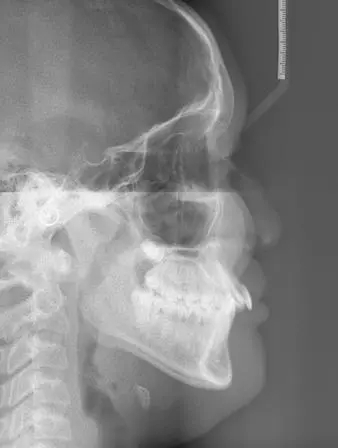

頭顱側(ce) 位片

而拍頭顱側(ce) 位片主要是為(wei) 了很好的測量頜骨的畸形程度,分析原因,判斷是屬於(yu) 單純的牙齒問題,還是屬於(yu) 頜骨異常造成的,這個(ge) 判斷重要,涉及到采用不同的矯正方式以及不同的矯治難易程度。拍頭顱側(ce) 位片的價(jia) 格目前大致在一兩(liang) 百元左右。